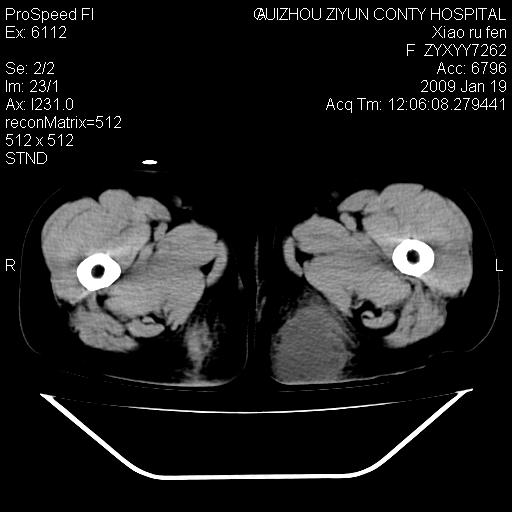

以下是引用zbp537在2009-1-19 14:25:00的发言:[br]考虑两个诊断:1、皮脂腺囊肿伴感染。2、脓肿。[br]诊断依据:[br]1、肿块为低密度,边界较清,和皮肤相连,周围结构清晰,未见受累及。[br]2、诊断脓肿是因为其内密度不均匀,当然要结合病史,因为脓肿临床上肯定表现为红肿热痛,也希望楼主把病史提供全面些,这些便于讨论。

以下是引用zbp537在2009-1-19 14:25:00的发言:[br]考虑两个诊断:1、皮脂腺囊肿。2、脓肿。[br]诊断依据:[br]1、肿块为低密度,边界较清,和皮肤相连,周围结构清晰,未见受累及。[br]2、诊断脓肿是因为其内密度不均匀,当然要结合病史,因为脓肿临床上肯定表现为红肿热痛,也希望楼主把病史提供全面些,这些便于讨论。